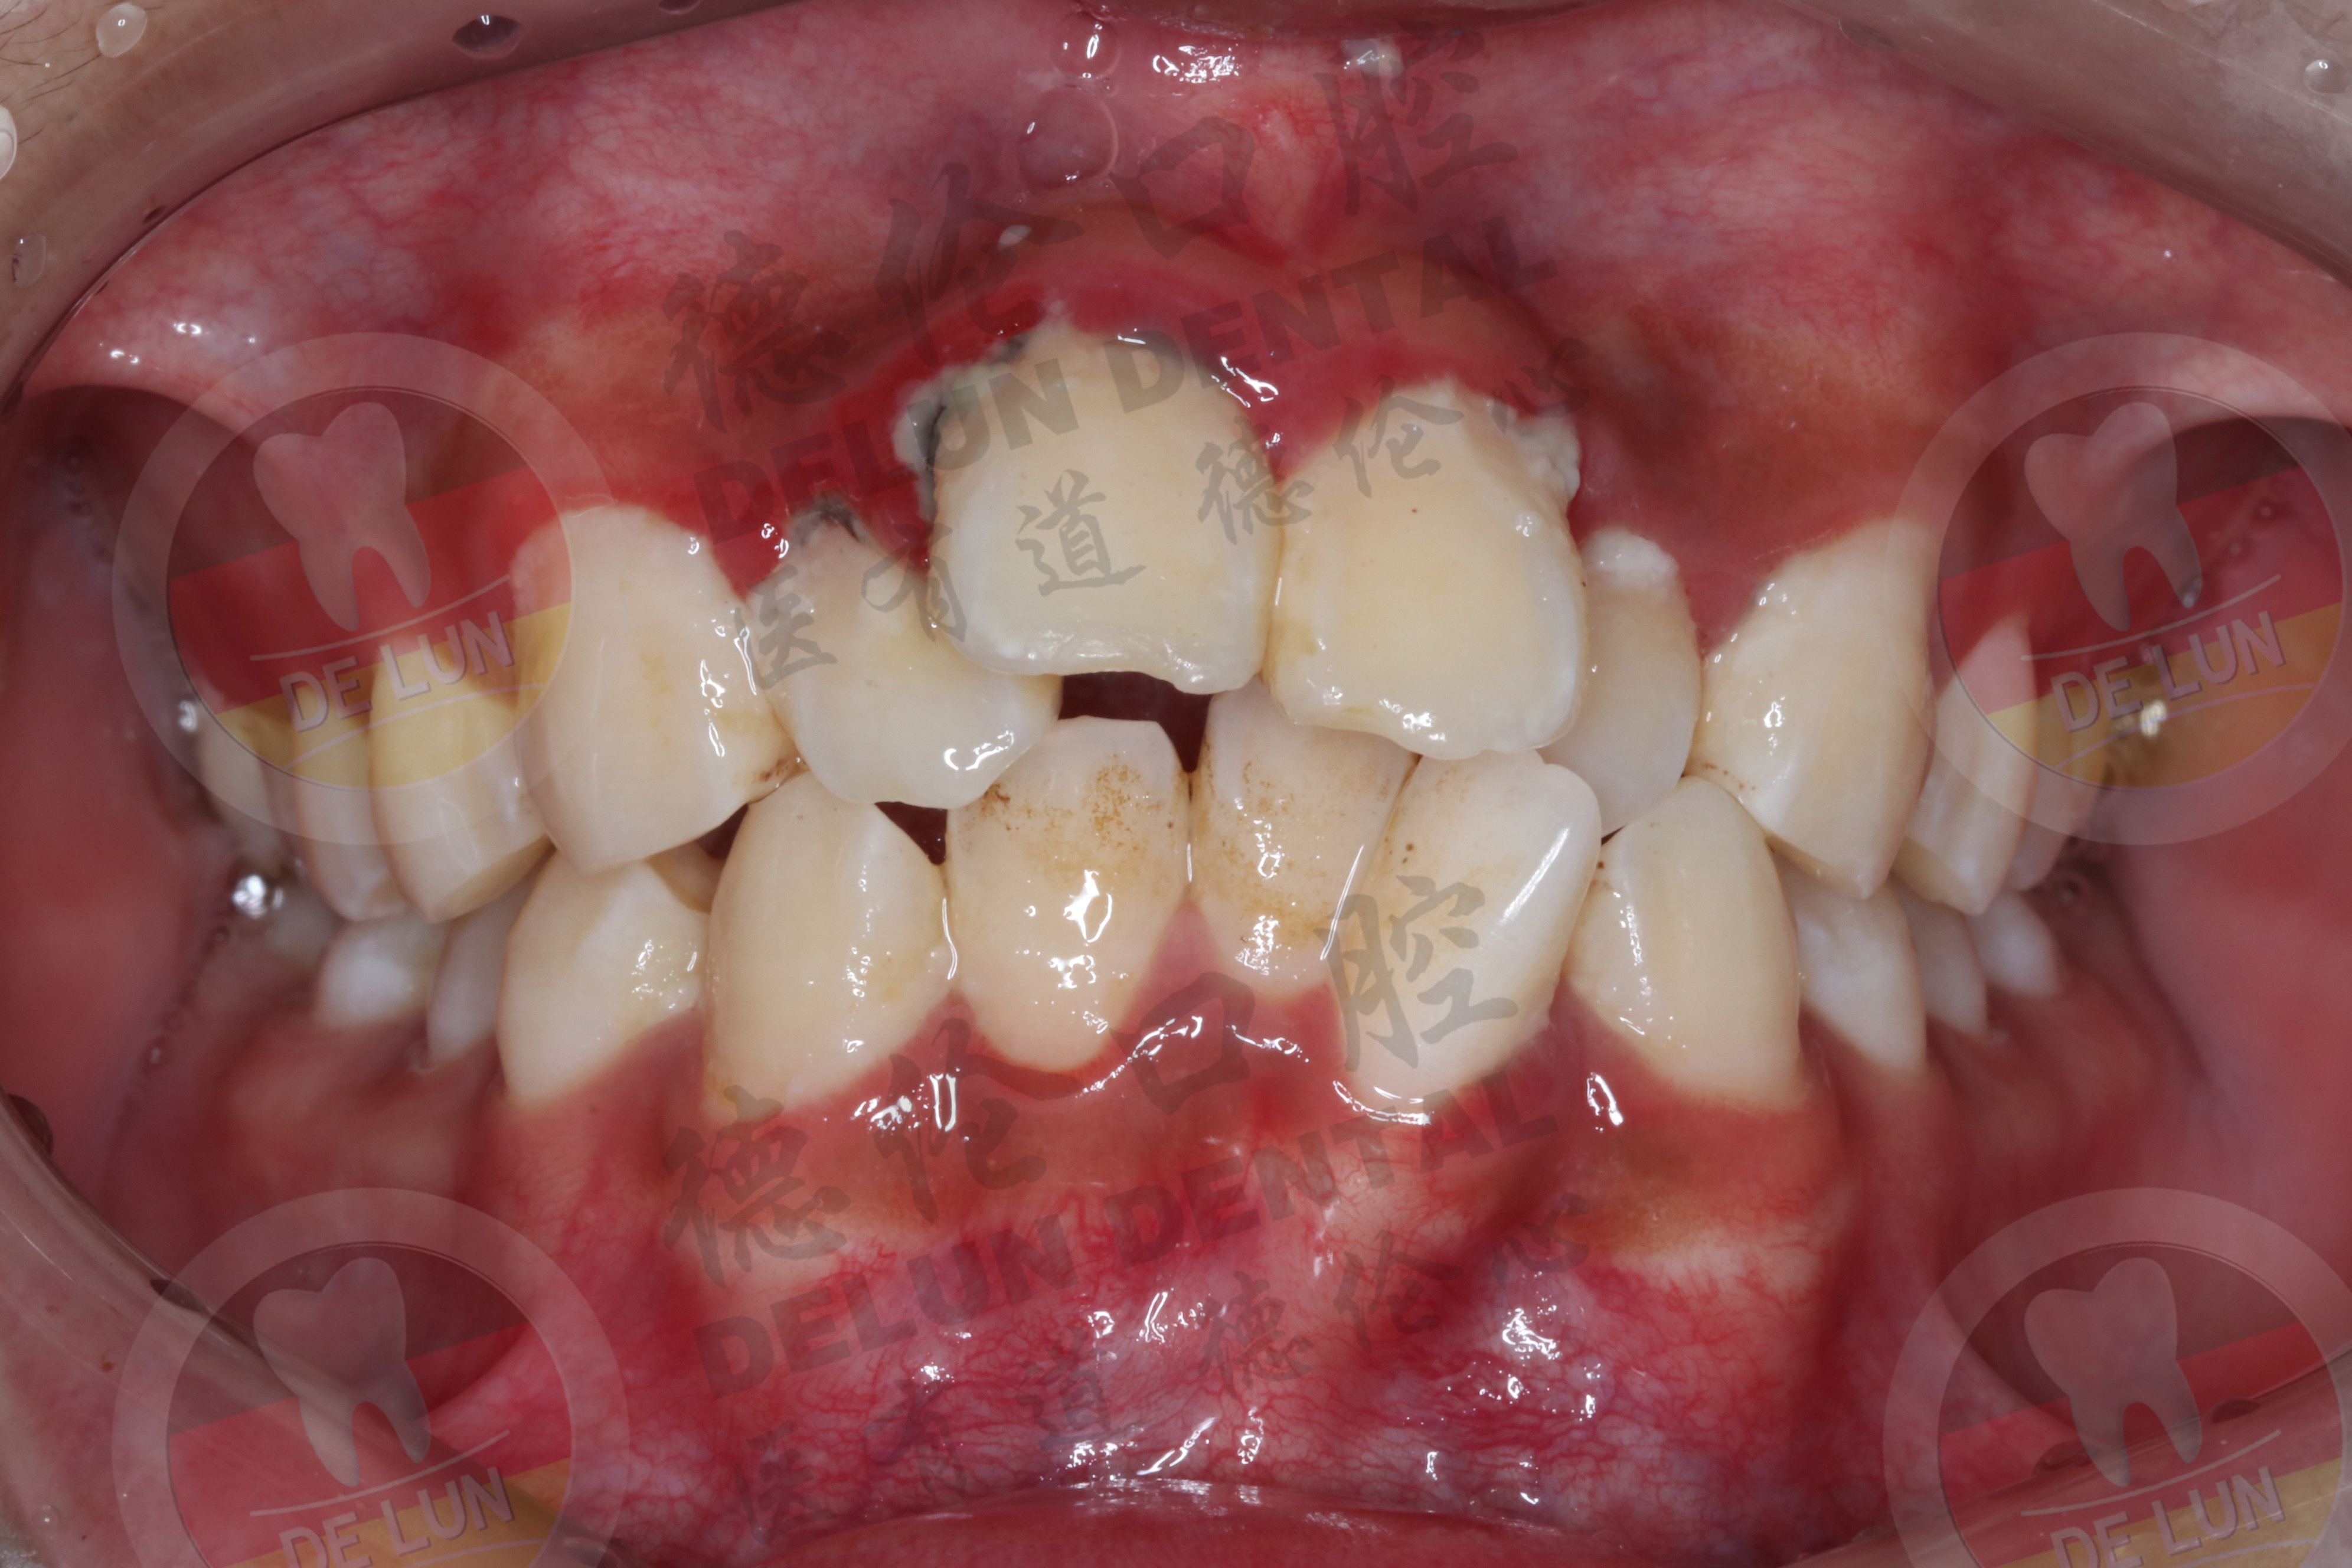

牙齿对于机体来说十分重要,对饮食以及内脏功能都会造成影响。在刷牙和进食时牙齿容易出现酸软的情况,通常是由于有龋齿、牙齿不齐、牙周炎、牙龈萎缩等造成的。

1.龋齿:在日常饮食中没有做到按时刷牙,食物长期累积在牙齿中很容易造成龋齿,龋齿是导致牙齿酸软的常见原因之一。主要是由于牙髓神经暴露容易受到外界刺激,引起牙酸不适。

2.牙齿不齐:在机体发育的过程中,牙齿可能出现不齐的情况,牙齿不齐会对周边牙齿的牙龈造成一定的影响,因此牙齿也会出现酸软的情况。

3.牙周炎:通常牙周炎的患者在早晨刷牙时会出现出血的现象,同时在咀嚼东西时会出现酸痛感,而且牙龈也有红肿的现象。

4.牙龈萎缩:生理性萎缩和病理性萎缩现象都会导致牙齿出现酸软的症状。这主要是由于牙周神经末梢极易受到冷、热等不良物理因素刺激导致的。